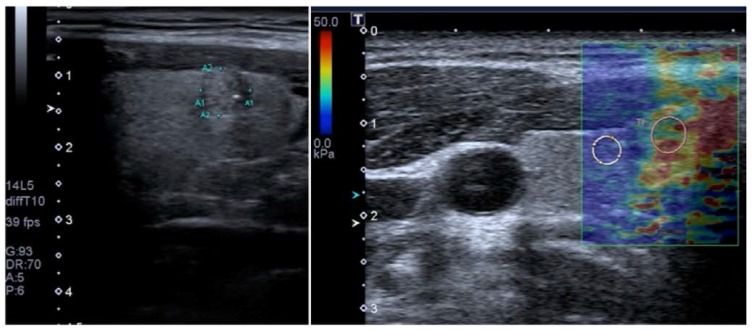

برخلاف تصویربرداری کرنش، SWI گره های تیروئید اندازه گیری های کمی را ارائه می دهد (شکل 9). تعدادی از متاآنالیزهای اخیر SWI نتایج امیدوارکنندهای را در 92-95 نشان دادهاند، با شباهتهای بین نتایج حداقل تا حدی به دلیل همپوشانی قابلتوجه در مطالعات وارد شده. Zhan و همکاران شامل مطالعات pSWE و بزرگترین متاآنالیز (2436 گره تیروئید) بودند. آنها دریافتند که pSWE برای افتراق ندول های خوش خیم از بدخیم مفید است (میانگین حساسیت = 80٪، میانگین ویژگی = 85٪، جدول 3) 3) 92. متاآنالیز توسط Dong و همکاران همچنین شامل مطالعات pSWE بود و نتایج مشابه خوبی پیدا کرد. 1617 ندول تیروئید، حساسیت تلفیقی = 86.3٪، ویژگی تلفیقی = 89.5٪

تصویر حالت B عرضی (سمت چپ) ندول ناهمگن تیروئید کوچک (ضایعه در ناحیه مورد نظر) با حاشیه های نامشخص و میکروکلسیفیکاسیون در لوب تیروئید راست را نشان می دهد که نشان دهنده علت بدخیم است. الاستوگرام رنگی مربوطه به دست آمده با 2D-SWE روی توشیبا آپلیو 500 (سمت راست) سفتی افزایش یافته ندول (ROI صورتی؛ 32.7 کیلو پاسکال) را در مقایسه با پارانشیم طبیعی اطراف (ROI سفید؛ 7.4 کیلو پاسکال) نشان می دهد که نشان می دهد ندول بدخیم است. بیوپسی بعدی کارسینوم پاپیلاری را تایید کرد.